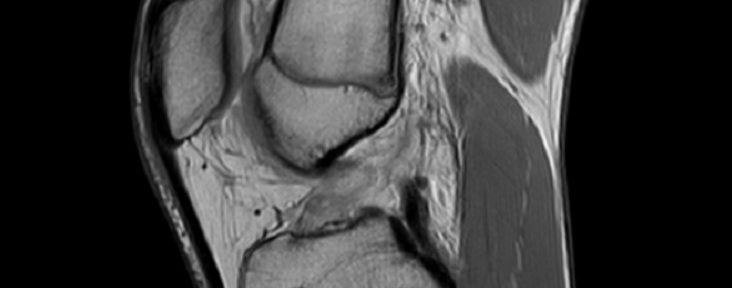

- Date: 2 August 2023 (MRI #2)

- Independent readings (3 radiologists): unanimous, ACLOAS grade 2.

- Findings: continuity restored; not full thickness, but definite thickness and tension obtained.

[ACLOAS (native ACL) notes] 0 = normal (low signal, regular); 1 = thickening/intra-ligament high signal with preserved shape and continuity; 2 = thinning/elongation with preserved continuity; 3 = discontinuity (defect).